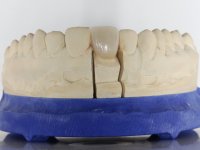

A pre-print was performed to make a crown in dual-cured resin. After a cross-section with a turbine, the infiltrated crown was removed with a microluxador. The dental stump was re-prepared to better define the shape and location of the cervical margin. It was necessary to place composite resin on the buccal surface of the provisional crown to improve its esthetics. The impression was made using a double-mix technique with two-viscosity, quick-setting silicones. In the laboratory, a crown with a ceramic-coated Zr infrastructure was made. After placing it in the mouth, we verified that the crown showed a greater translucency than the symmetrical one, not fulfilling our aesthetic goals. The ceramist had the opportunity to observe the situation in the clinic, collecting records for later rectification. The new crown was placed in the mouth and approved by the patient. The final cementation was done with resin-reinforced glass ionomer cement.